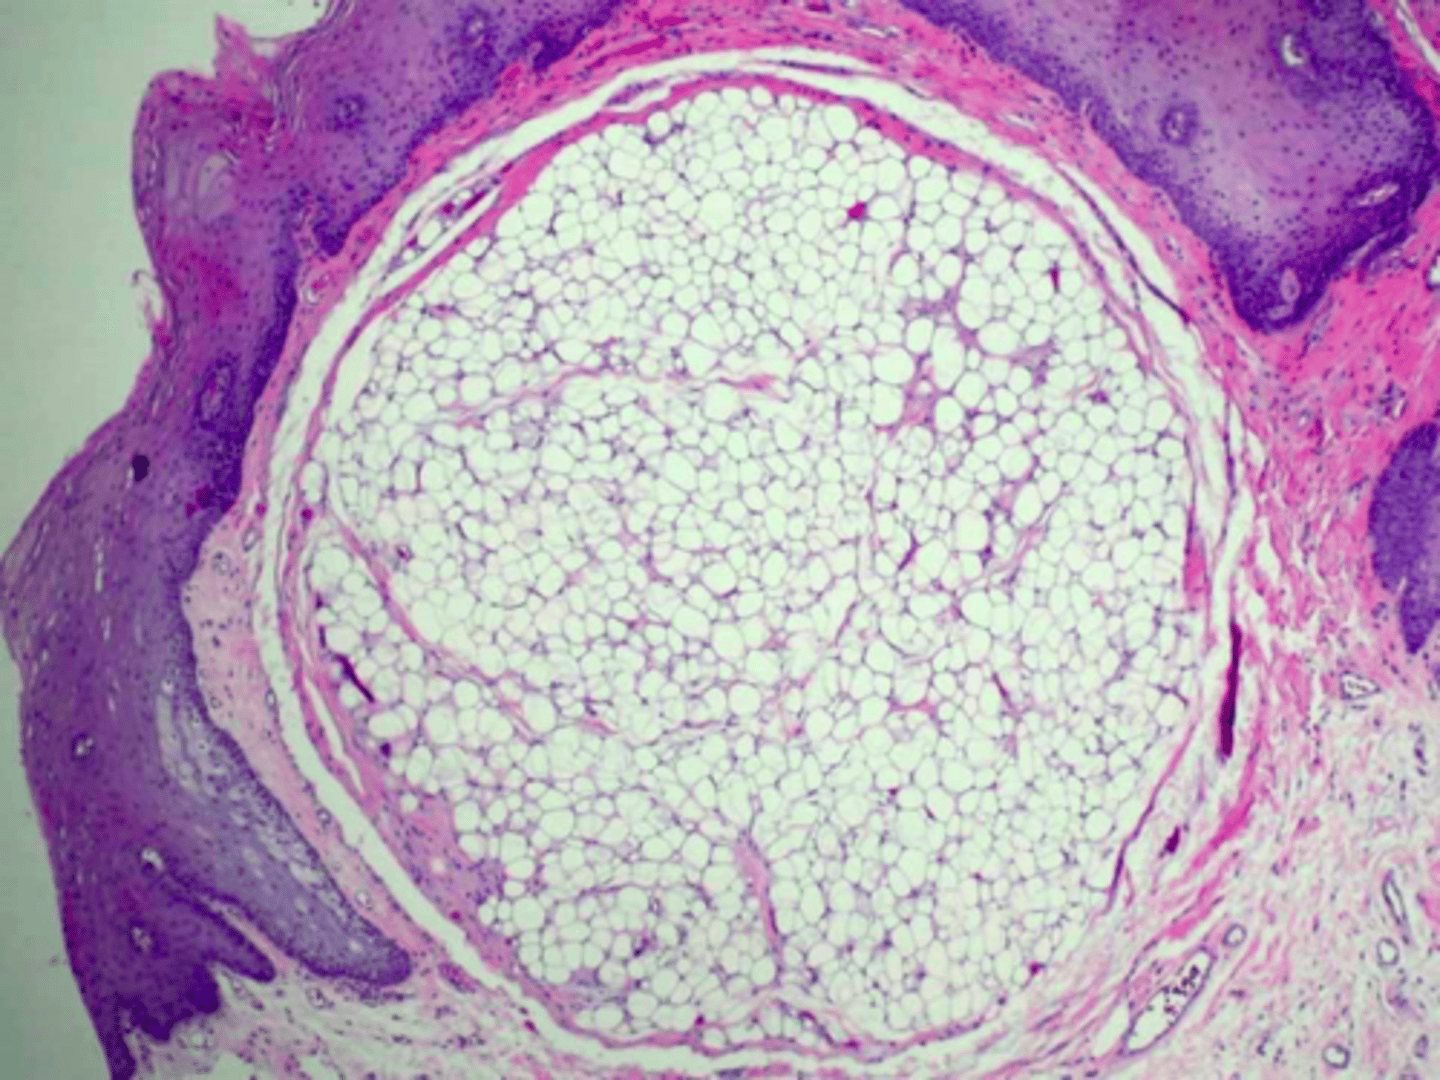

Lipoma

patient presents with nodule on the floor of the mouth that is and slight yellowish tint. Histopathology showed Well-circumscribed mature adipose tissue. What do you suspect?

Lipoma

ID the pathology: